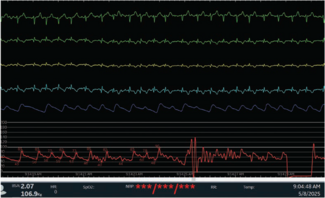

Vagal responses, while mostly benign, should never be neglected or overlooked as unimportant, or worse, ignored until a real disaster is present. Such could have been the case with the patient we worked with recently.